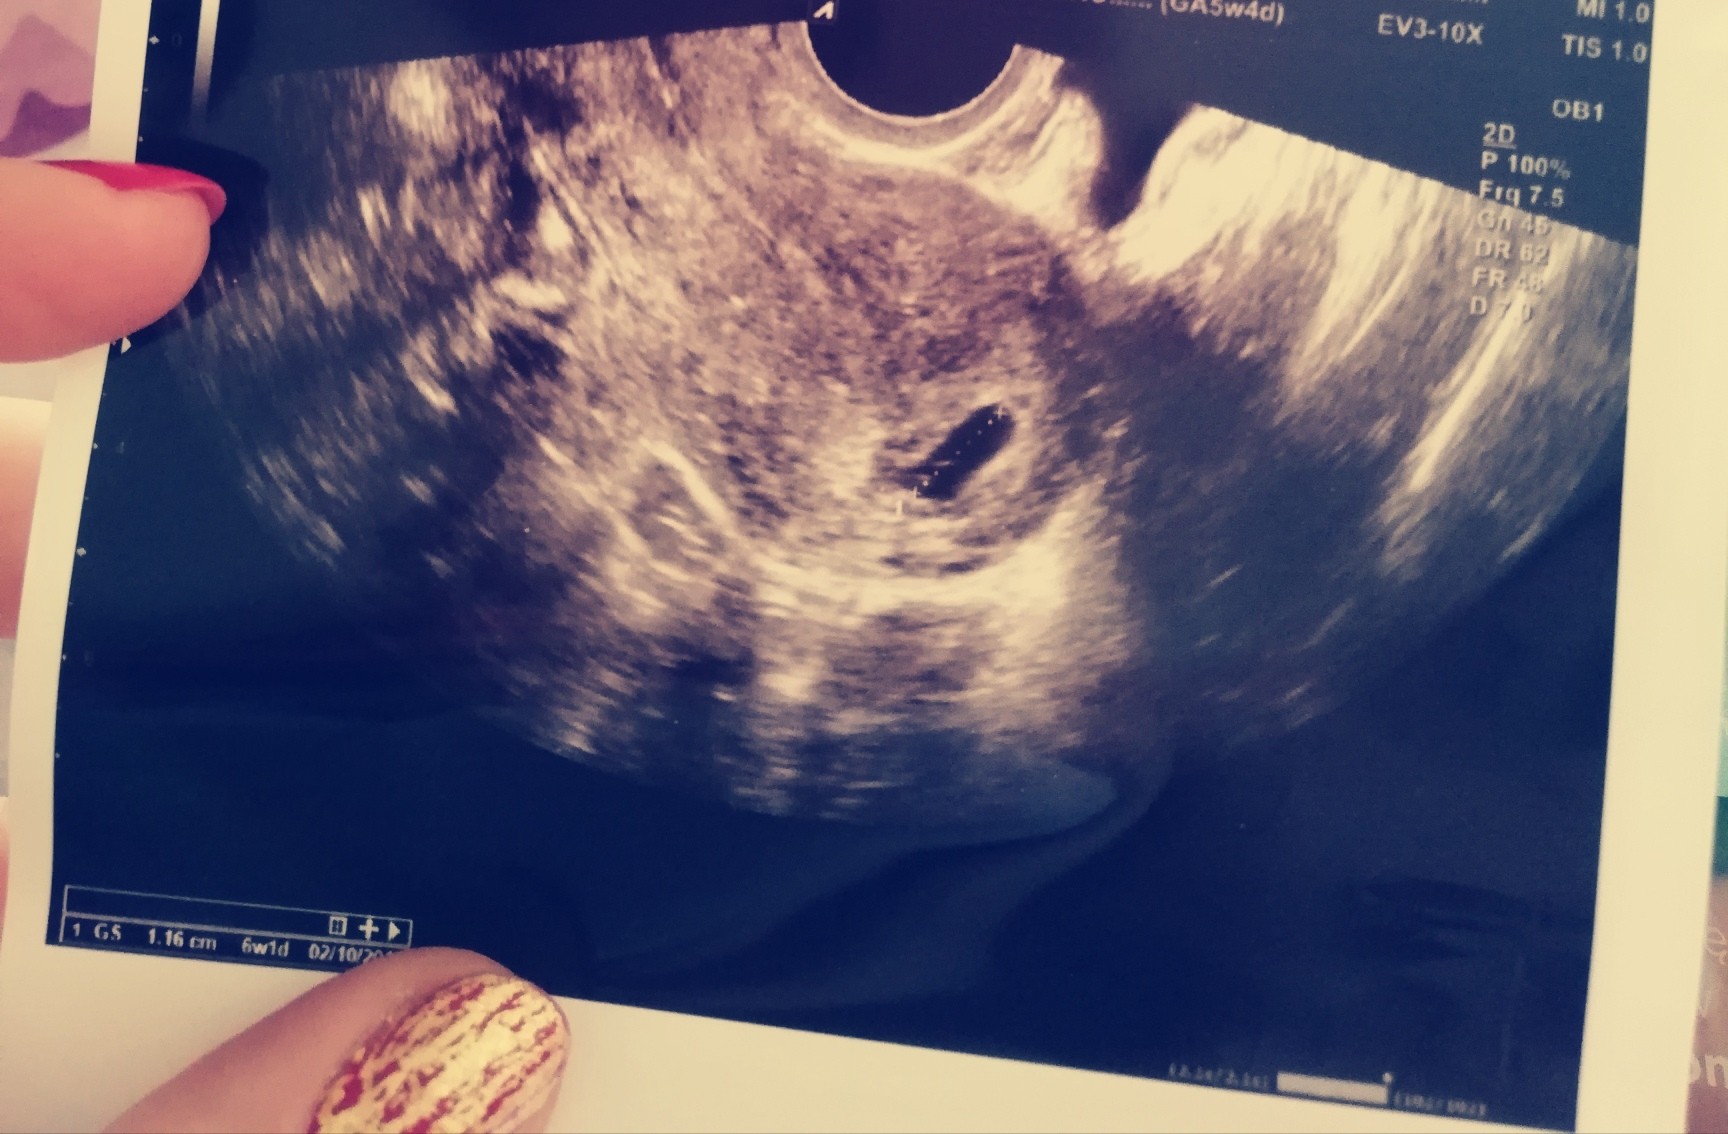

jaa aktualnie w 6 tygodniu. Moje usg w 5 tygodniu, ktore dodam bylo dla mnie szokiem może dlatego ,ze był pęcherzyk 1.16cm a zarodek 1.8mm ale serduszko jeszcze nie biło...kolejne usg 21 mam nadzieje ze już zobaczę wieksza dzidzie z bijacym serduszkiem. A jak u was. Juz po USG?Zobacz załącznik 941785